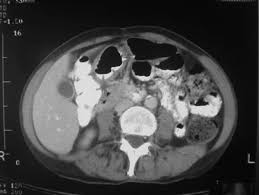

Does anybody know if they can tell the difference between diverticulitis and colon cancer on a ct scan? During diverticulitis, diverticula become infected or inflamed. Although at first diverticulitis and colon cancer may present similar symptoms, they are two very different conditions. Primary colonic gi lymphomas (usually diffuse large b cell), however, can be mistaken for ibd on colonoscopy. Most times it occurs when small pouches called diverticula become infected or swollen.

Diverticulitis is a condition set off by infection or rupture of diverticula,. Sure, a ct scan can be consistent with diverticulitis, but many other conditions can precisely mimic this ct scan appearance. I was diagnosed with diverticulitis with a severe infection; It does not appear that diverticulitis and cancer are heavily linked, as the former is a very common condition that is generally easily treated. Symptoms of diverticulitis and colon cancer may include abdominal pain. The most frequent issues with the bowel or colon, affect the colon's ability to work properly. August 8, 2009 at 12:09 pm. Yes diverticulosis is benign, has distinct appearance from ca on ct for a trained radiologist will read as accurate as reading finger prints, some times in between diverticula the wall may be thickened, may have mucosal overgrowth will mimic a early cancer, then colonoscopy indicated, at 39 cancer is not common but age is not exception for ca, ask again for referral. Diverticulitis involves common digestive tract growths called diverticula. Screening for colon cancer can detect and remove precancerous polyps before they have the chance to develop into cancer. Patients who present with acute diverticulitis may have significant abdominal pain and fever, which may be confused with inflammatory bowel disease or peptic ulcer disease. When colonic obstruction is present, colon cancer is more likely than diverticulitis. Although at first diverticulitis and colon cancer may present similar symptoms, they are two very different conditions.